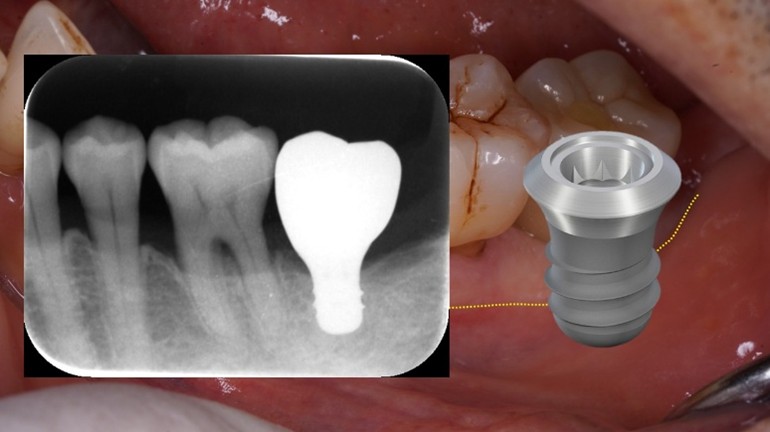

6㎜の長さのショートインプラントで治療することを決定

歯周病で歯を失った部分はすでに大きく骨がやせています。当院では骨造成などの処置も行っていますが、大掛かりな手術になるほどどうしても術後の腫れや痛み、長い治療期間が避けられなくなります。今回は6㎜という短い長さのインプラントで対応することにしました。

手術後腫れや痛みもほとんどなく、手術時間も約15分で済みました。